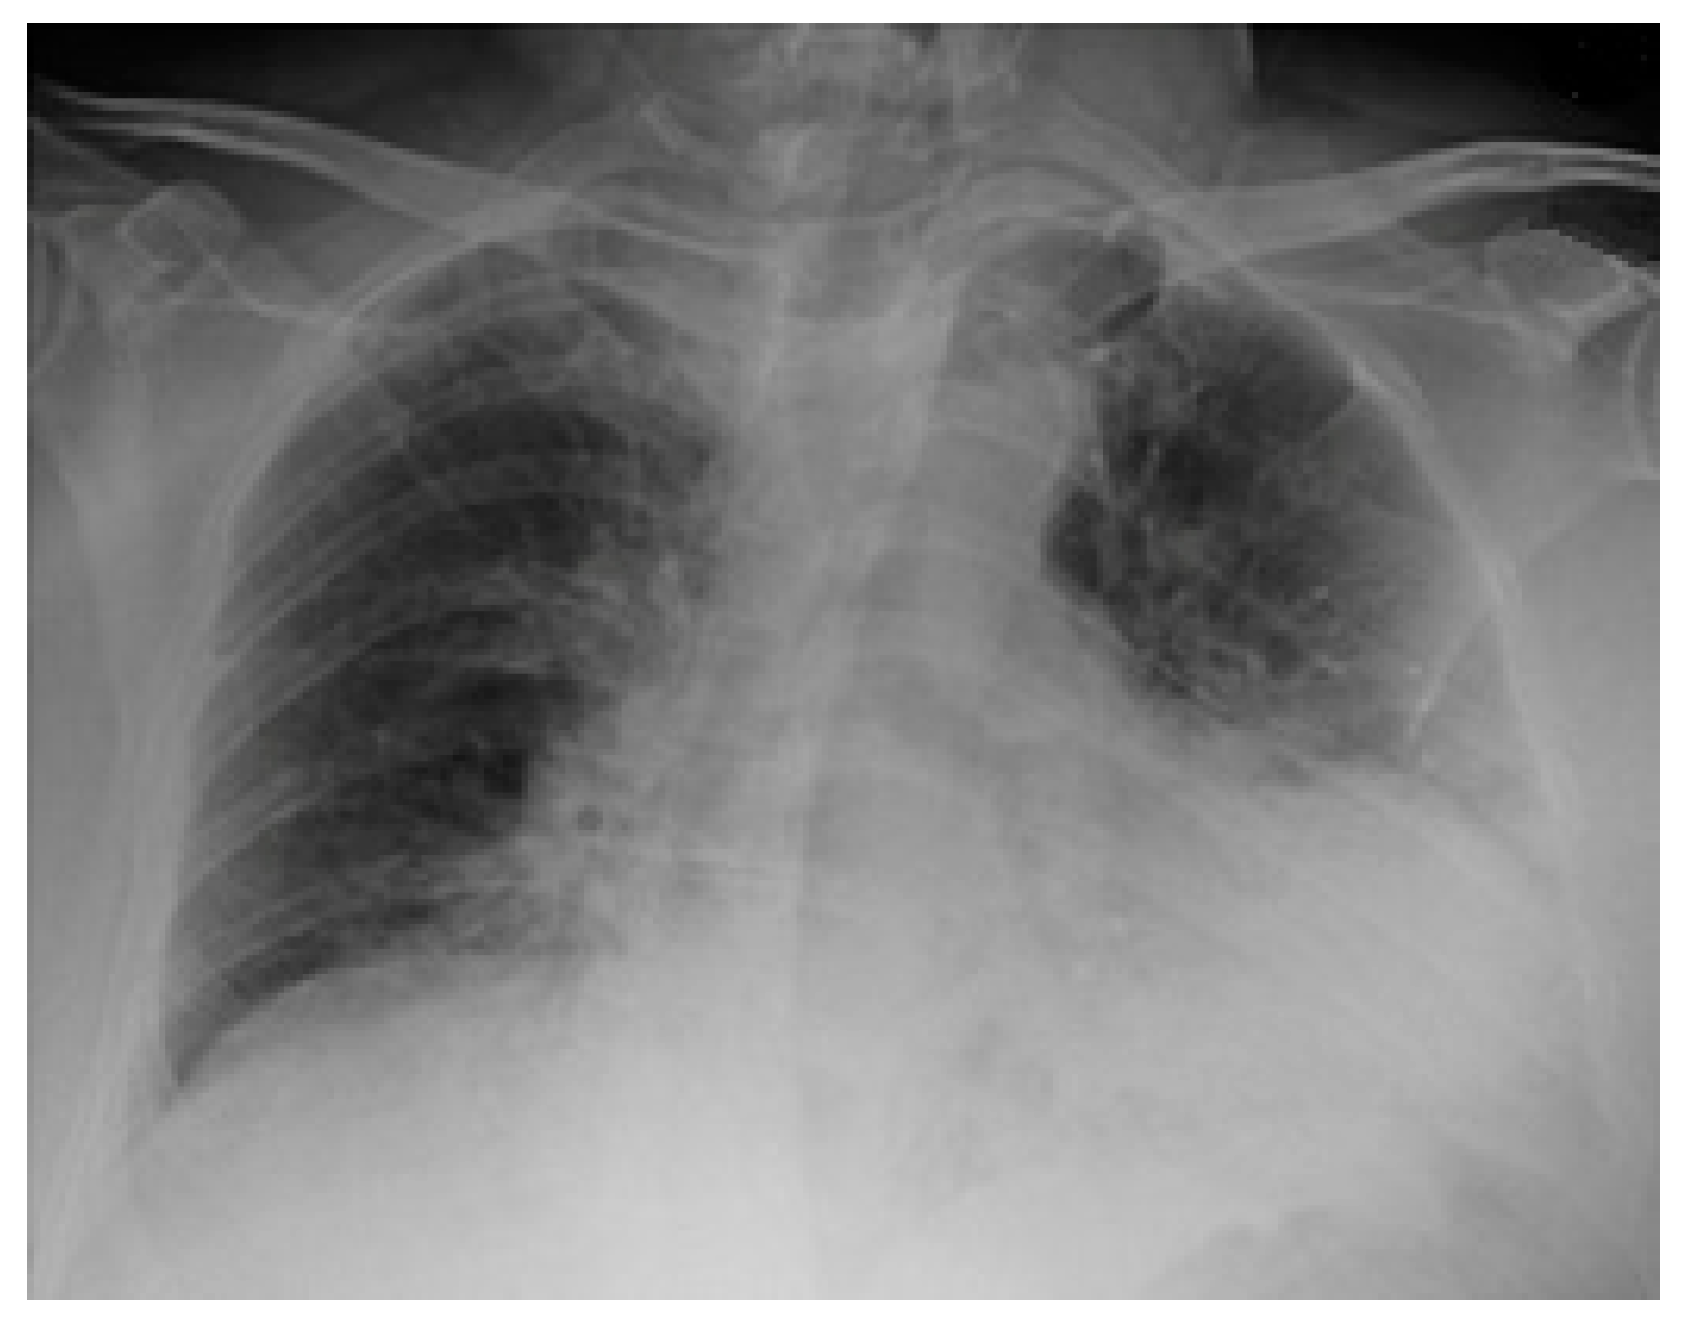

2.3. Imaging and Analysis

3. Results